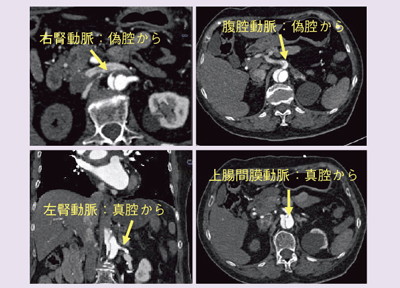

●症例2:急性大動脈解離

Definition Flashは,救急疾患においても有用性を発揮する。図5,6は胸痛,心筋梗塞疑いで緊急搬送された症例で,アンギオ室搬入前の超音波検査で,大動脈にintima flapを認め大動脈解離が疑われたため,CT撮影となった。図5aで,上行大動脈にflapが認められ,さらに,通常CTではとらえることが難しいEntryが確認でき(図5b〜d),逆行性解離と順行性解離の両方を持った解離であることがわかる。

同時に腹部の情報も得ることができ(図6),右腎動脈が偽腔から出ており,濃染が不良なことから閉塞していると考えられる。また,左腎動脈,上腸間膜動脈は真腔から,腹腔動脈は偽腔から出ていることも確認できたが,冠動脈に有意狭窄が認められなかったことから,手術適応のStanford Type Aと判断し,緊急手術となった。

![]() 図5 症例2:急性大動脈解離(Stanford Type A) |

![]() 図6 症例2:急性大動脈解離(腹部) |